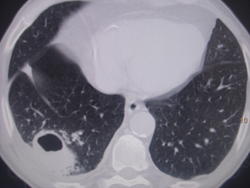

Больной лечился у невролога, провели проф ФГ- выявили деструктивную пневмонию, пролечилили, на Р контроле- ухудшение, клиники абсцесса не было, была боль в гр клетке спереди справа. Из анамнеза- лечился оперативно 6-7 лет назад по поводу рака верхней губы, в ООД не наблюдался последние годы. Данные за туб этиологию сомнительны, как мне кажется, очагов отсева по слоям не вижу,  хотя мож не так смотрю. Ваше мнение коллеги, абсцесс это или нет?

Вполне может быть и полостной формой рака с периканкрозной пневмонией. Пока исследуют мокроту на БК, АК и микрофлору с чувствительностью к антибиотикам, пока лечат, придёт время и для КТ-контроля после лечения. В зависимости от рукастости хирургов, можно было б и пропунктировать - но тут в каждом монастыре свой устав)).

По опыту хочу сказать, что в настоящее время классической клиники абсцесса можете и не увидеть. Очень она изменилась. В данном случае контроль  должен помочь. В связи с тем, что стенки имеют разную толщину и вокруг почти нет изменений, больше склоняюсь к полостной форме рака.